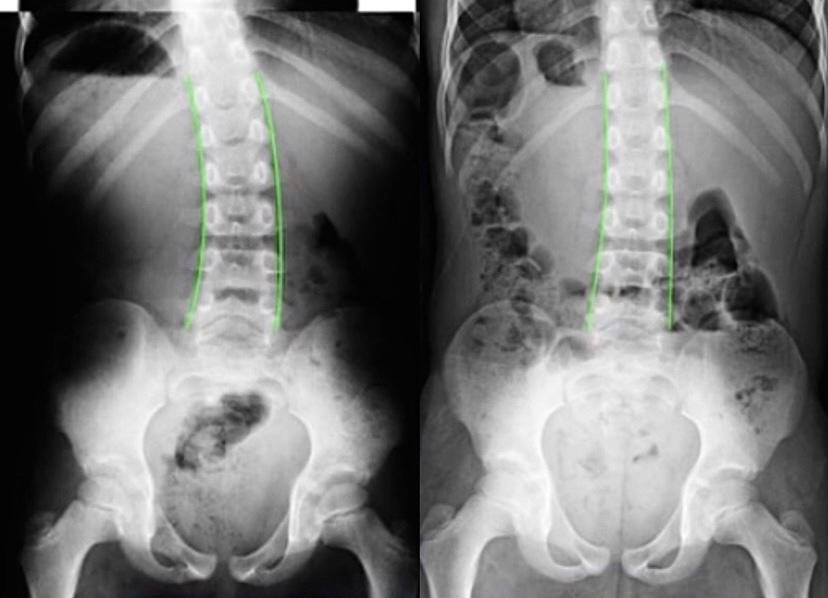

下部胸椎過剰後弯の改善例(側面像)

健康と美容に対して意識の高い40代女性。

軽度の側彎症と下部胸椎の後弯(側面増)でお悩みの女性よりご相談を受けました。特別この部分に痛みや違和感などはないようでしたが、見た目が気になる、というこの女性のお悩みは深刻なものでした。痛みや違和感のない状態で、また健康を害することなく内部の機能を考慮しながら構造的な変化を齎す、ということはとても難しいものとなります。構造的、機能的な部分を考慮し対応した結果となりますが、施術の途中よりお引越しが決まり他院へのご紹介となりました。

※これは個人の感想と画像の結果であり施術の効果を保障するものではありません。また効果には個人差があります。